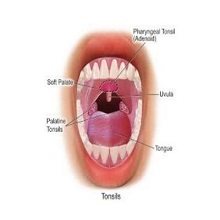

„Крајници су прва одбрана и заштита од вируса и бактерија тако је било раније", напомиње начелник ОРЛ одељења доктор Вељко Божић и додаје да углавном виђају крајнике који се нису ни развили већ представљају могућност да се развијају бактеријске инфекције. Зато су међу најчешћим операције крајника на хирушком Одељењу за ухо, грло и нос |